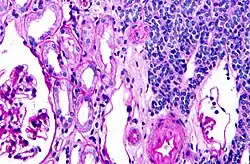

Micrograph of a metanephric adenoma (right of image). Normal kidney is seen on the left. Kidney biopsy. PAS stain.

Micrograph of a metanephric adenoma, right of image, showing the characteristic features (round nuclear membrane, no nucleoli, and fine chromatin). Normal kidney is seen on the left of the image. Kidney biopsy. PAS stain.

Metanephric adenoma is diagnosed histologically. The tumours can be located at upper pole, lower pole and mid-hilar region of the kidney; they are well circumscribed but unencapsulated, tan pink, with possible cystic and hemorrhagic foci. They show a uniform architecture of closely packed acinar or tubular structures of mature and bland appearance with scanty interposed stroma.[3][4][5][6][7] Cells are small with dark staining nuclei and inconspicuous nucleoli. Blastema is absent whereas calcospherites may be present. Glomeruloid figures are a striking finding, reminiscent of early fetal metenephric tissue. The lumen of the acini may contain otherwise epithelial infoldings or fibrillary material but it is quite often empty. Mitoses are conspicuously absent.[3][4][5][6][7] In the series reported by Jones et al. tumour cells were reactive for Leu7 in 3 cases of 5, to vimentine in 4 of 6, to cytocheratin in 2 of 6, to epithelial membrane antigen in 1 of 6 cases and muscle specific antigen in 1 of 6.[5] Olgac et al. found that intense and diffuse immunoreactivity for alpha-methylacyl-CoA racemase (AMACR) is useful in differentiating renal cell carcinoma from MA but a panel including AMACR, CK7 and CD57 is better in this differential diagnosis.[8] Differential diagnosis may be quite difficult indeed as exemplified by the three malignancies initially diagnosed as MA that later metastasized, in the report by Pins et al.[9]